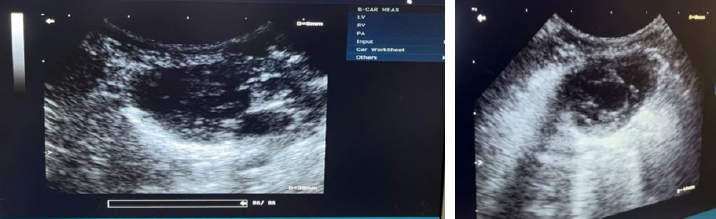

USG interpretation

The findings of USG performed in the dorsal recumbent position on the thoracic and abdominal regions revealed the existence of fluid accumulation in the peritoneal cavity (Fig. 4).

The abdominal cavity examination conducted through USG revealed certain structures appearing anechoic on the sonogram, indicating the presence of ascitic fluid in the abdominal cavity (Prajapati et al., 2022).

Fig. 4. The abdominal region of Hiro, a feline specimen, displays the presence of ascites as evidenced by medical imaging using USG.